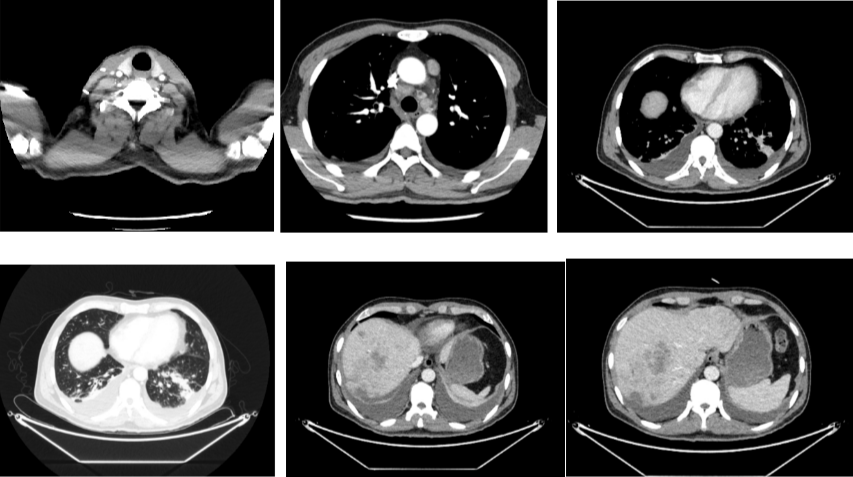

2020年4月复查:持续PR

肿瘤标志物:均正常

肝功能正常。

增强CT示:肝硬化

肝异常强化灶

考虑酒精性肝硬化可能性大,未基线使用替吉奥维持治疗。

胃癌并肝转移化疗后,肝内转移灶大致同期;

慢性肝病,脾大、门脉高压(食管下段-胃底静脉曲张);

右肺上叶前段实性微小结节,炎性结节?建议定期复查;

纵隔淋巴结转移瘤,复查大致同前。